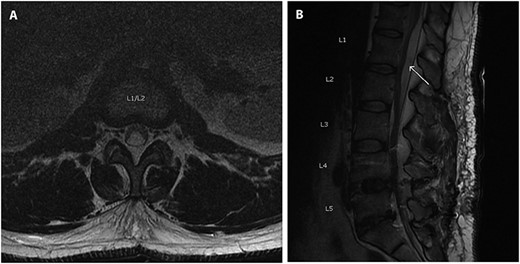

On post-operative day 2, the patient began having urinary retention, bilateral leg pain and numbness in the left L5 distribution. Magnetic resonance imaging (MRI) showed a T12-L2 subdural fluid collection measuring ~8 mm in depth and exerting a mass effect on the distal spinal cord and cauda equina (Fig. 2). The patient was urgently taken back to the operating room for L1-L2 decompressive laminectomy. The thecal sac was under considerable tension and when an incision was made through the dura, the cerebrospinal fluid (CSF) appeared to be under pressure. The epidural space was inspected and no hematoma was noted. A lumbar drain was left in the subdural space. The drain was kept in place for 3 days. The patient progressed well with his strength and sensation, except for some residual numbness in the left toes. The patient was discharged home.

Axial (A) and sagittal (B) T2 MRI scan obtained post-operatively showing a subdural hygroma (arrow), cephalad to the site of fusion, which caused symptoms of cauda equina syndrome.